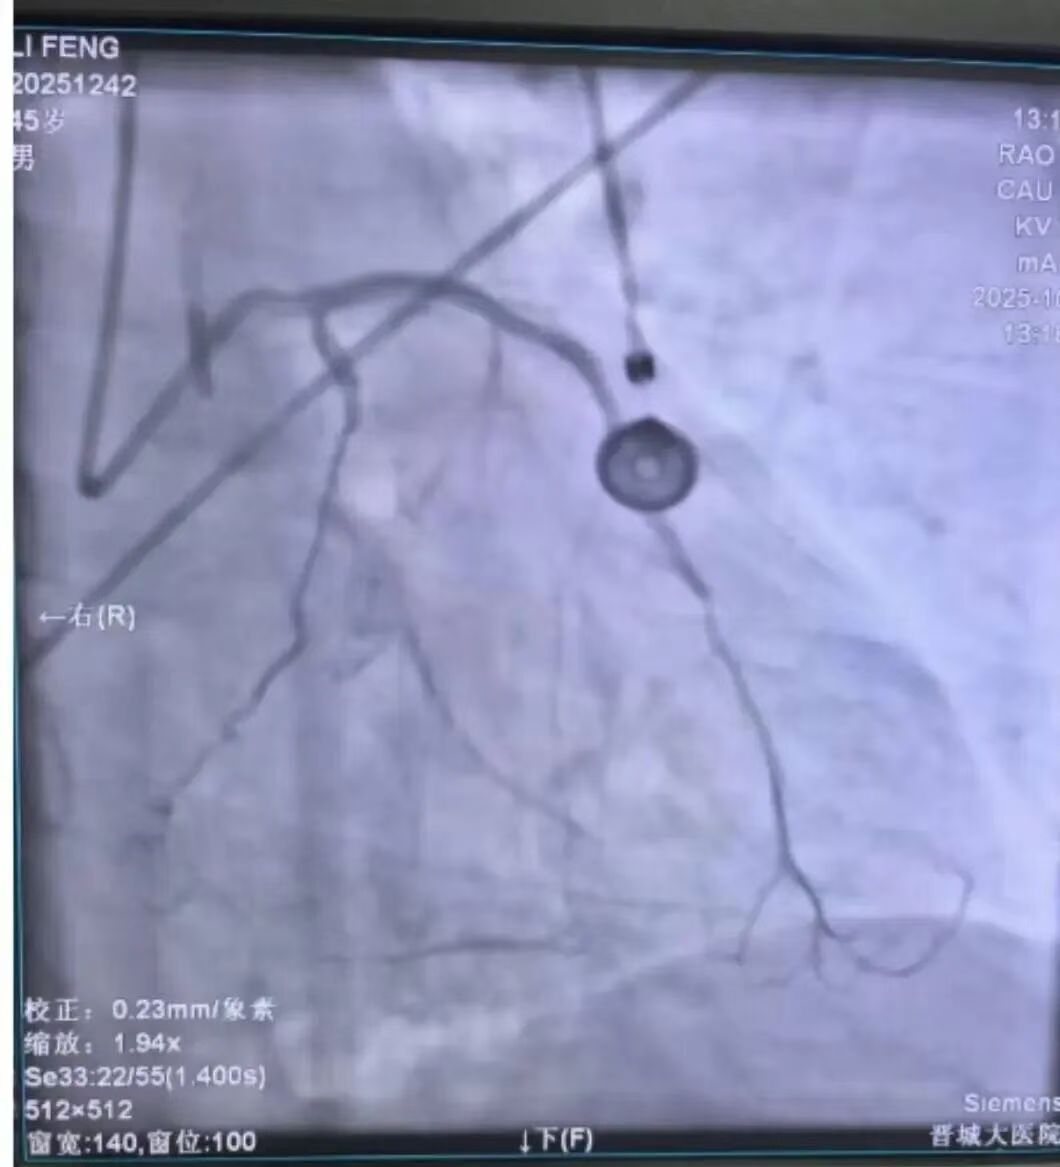

毋会芃副院长、崔少波院长助理带队,介入团队迅速为患者实施急诊冠脉介入治疗。手术精准指向本次心梗相关血管前降支,短短数分钟血管就被开通,并植入支架一枚,前向血流TIMI3级;同时在严重影响血流的回旋支近段置入支架一枚。

手术后